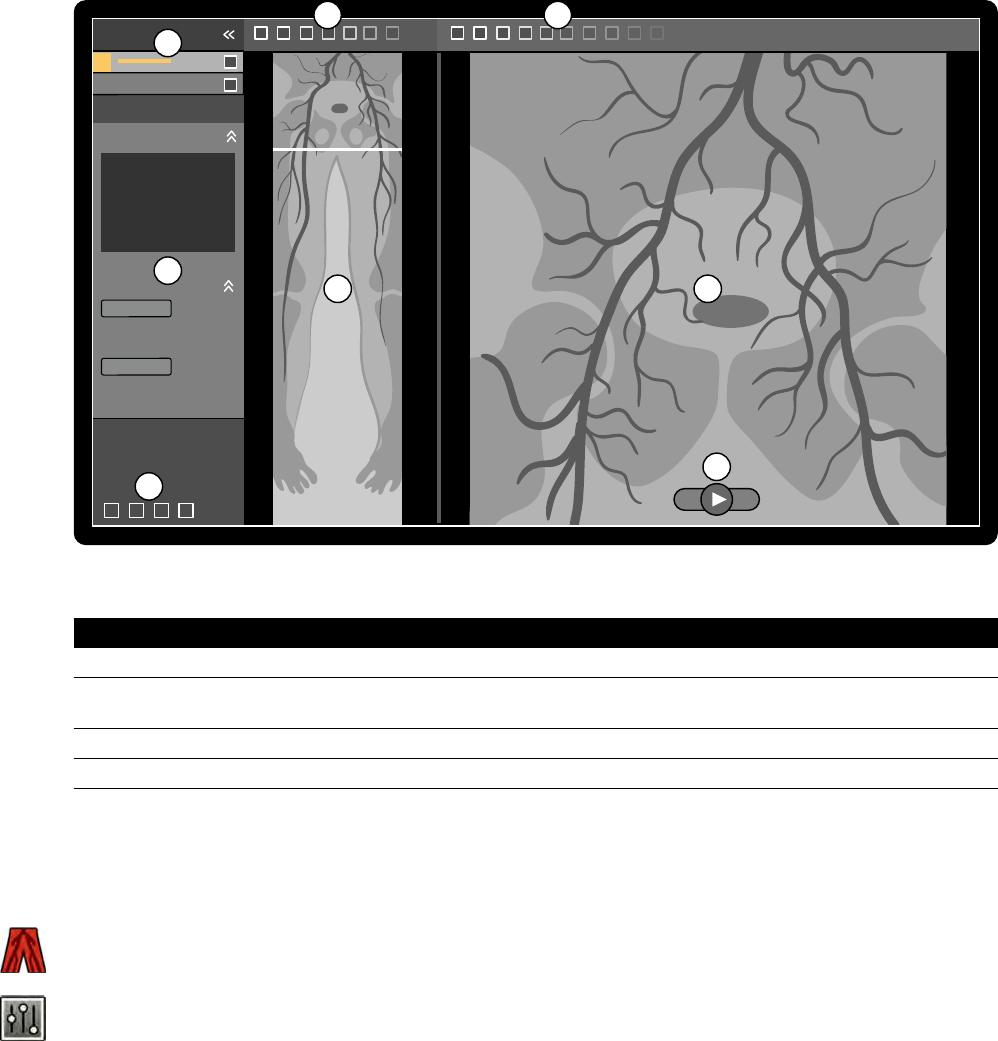

7.7 Rekonstrukcja z użyciem funkcji Bolus Chase....................................................................... 121

7.7.1 Zadania.................................................................................................................122

7.7.2 Rekonstrukcja.......................................................................................................122

7.7.3 Przetwarzanie.......................................................................................................126